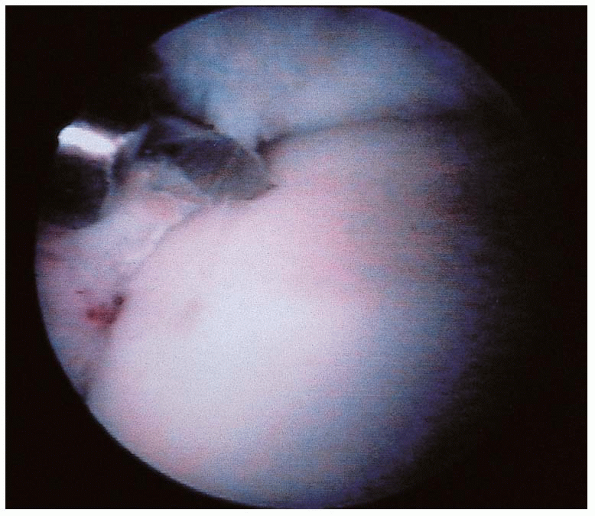

![]() |

FIGURE 31-21. Arthroscopic view of an anterolateral lesion of the talus.

easily accessible. They are approached with the scope placed medially

excised and the bed drilled with a small K-wire (Figs. 31-21, 31-22 and 31-23).